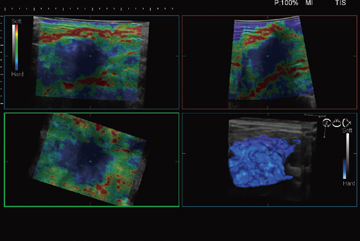

Real-time Tissue Elastographyは,組織の硬さの違いを画像化する技術で,2003年に日立が世界で初めて製品化した。現在では,乳がん検診をはじめとした日常検査でも使用されるようになってきている。「HI VISION Ascendus」には,リアルタイムでElastographyを3D表示する機能を搭載した(図2)。この機能は,リニア探触子を機械的に揺動させることでボリュームデータをリアルタイムに取得し,組織の硬さ情報を画像化する。この機能の実現には高速の信号処理能力が要求され,Ultra BEUにより初めて実現した。